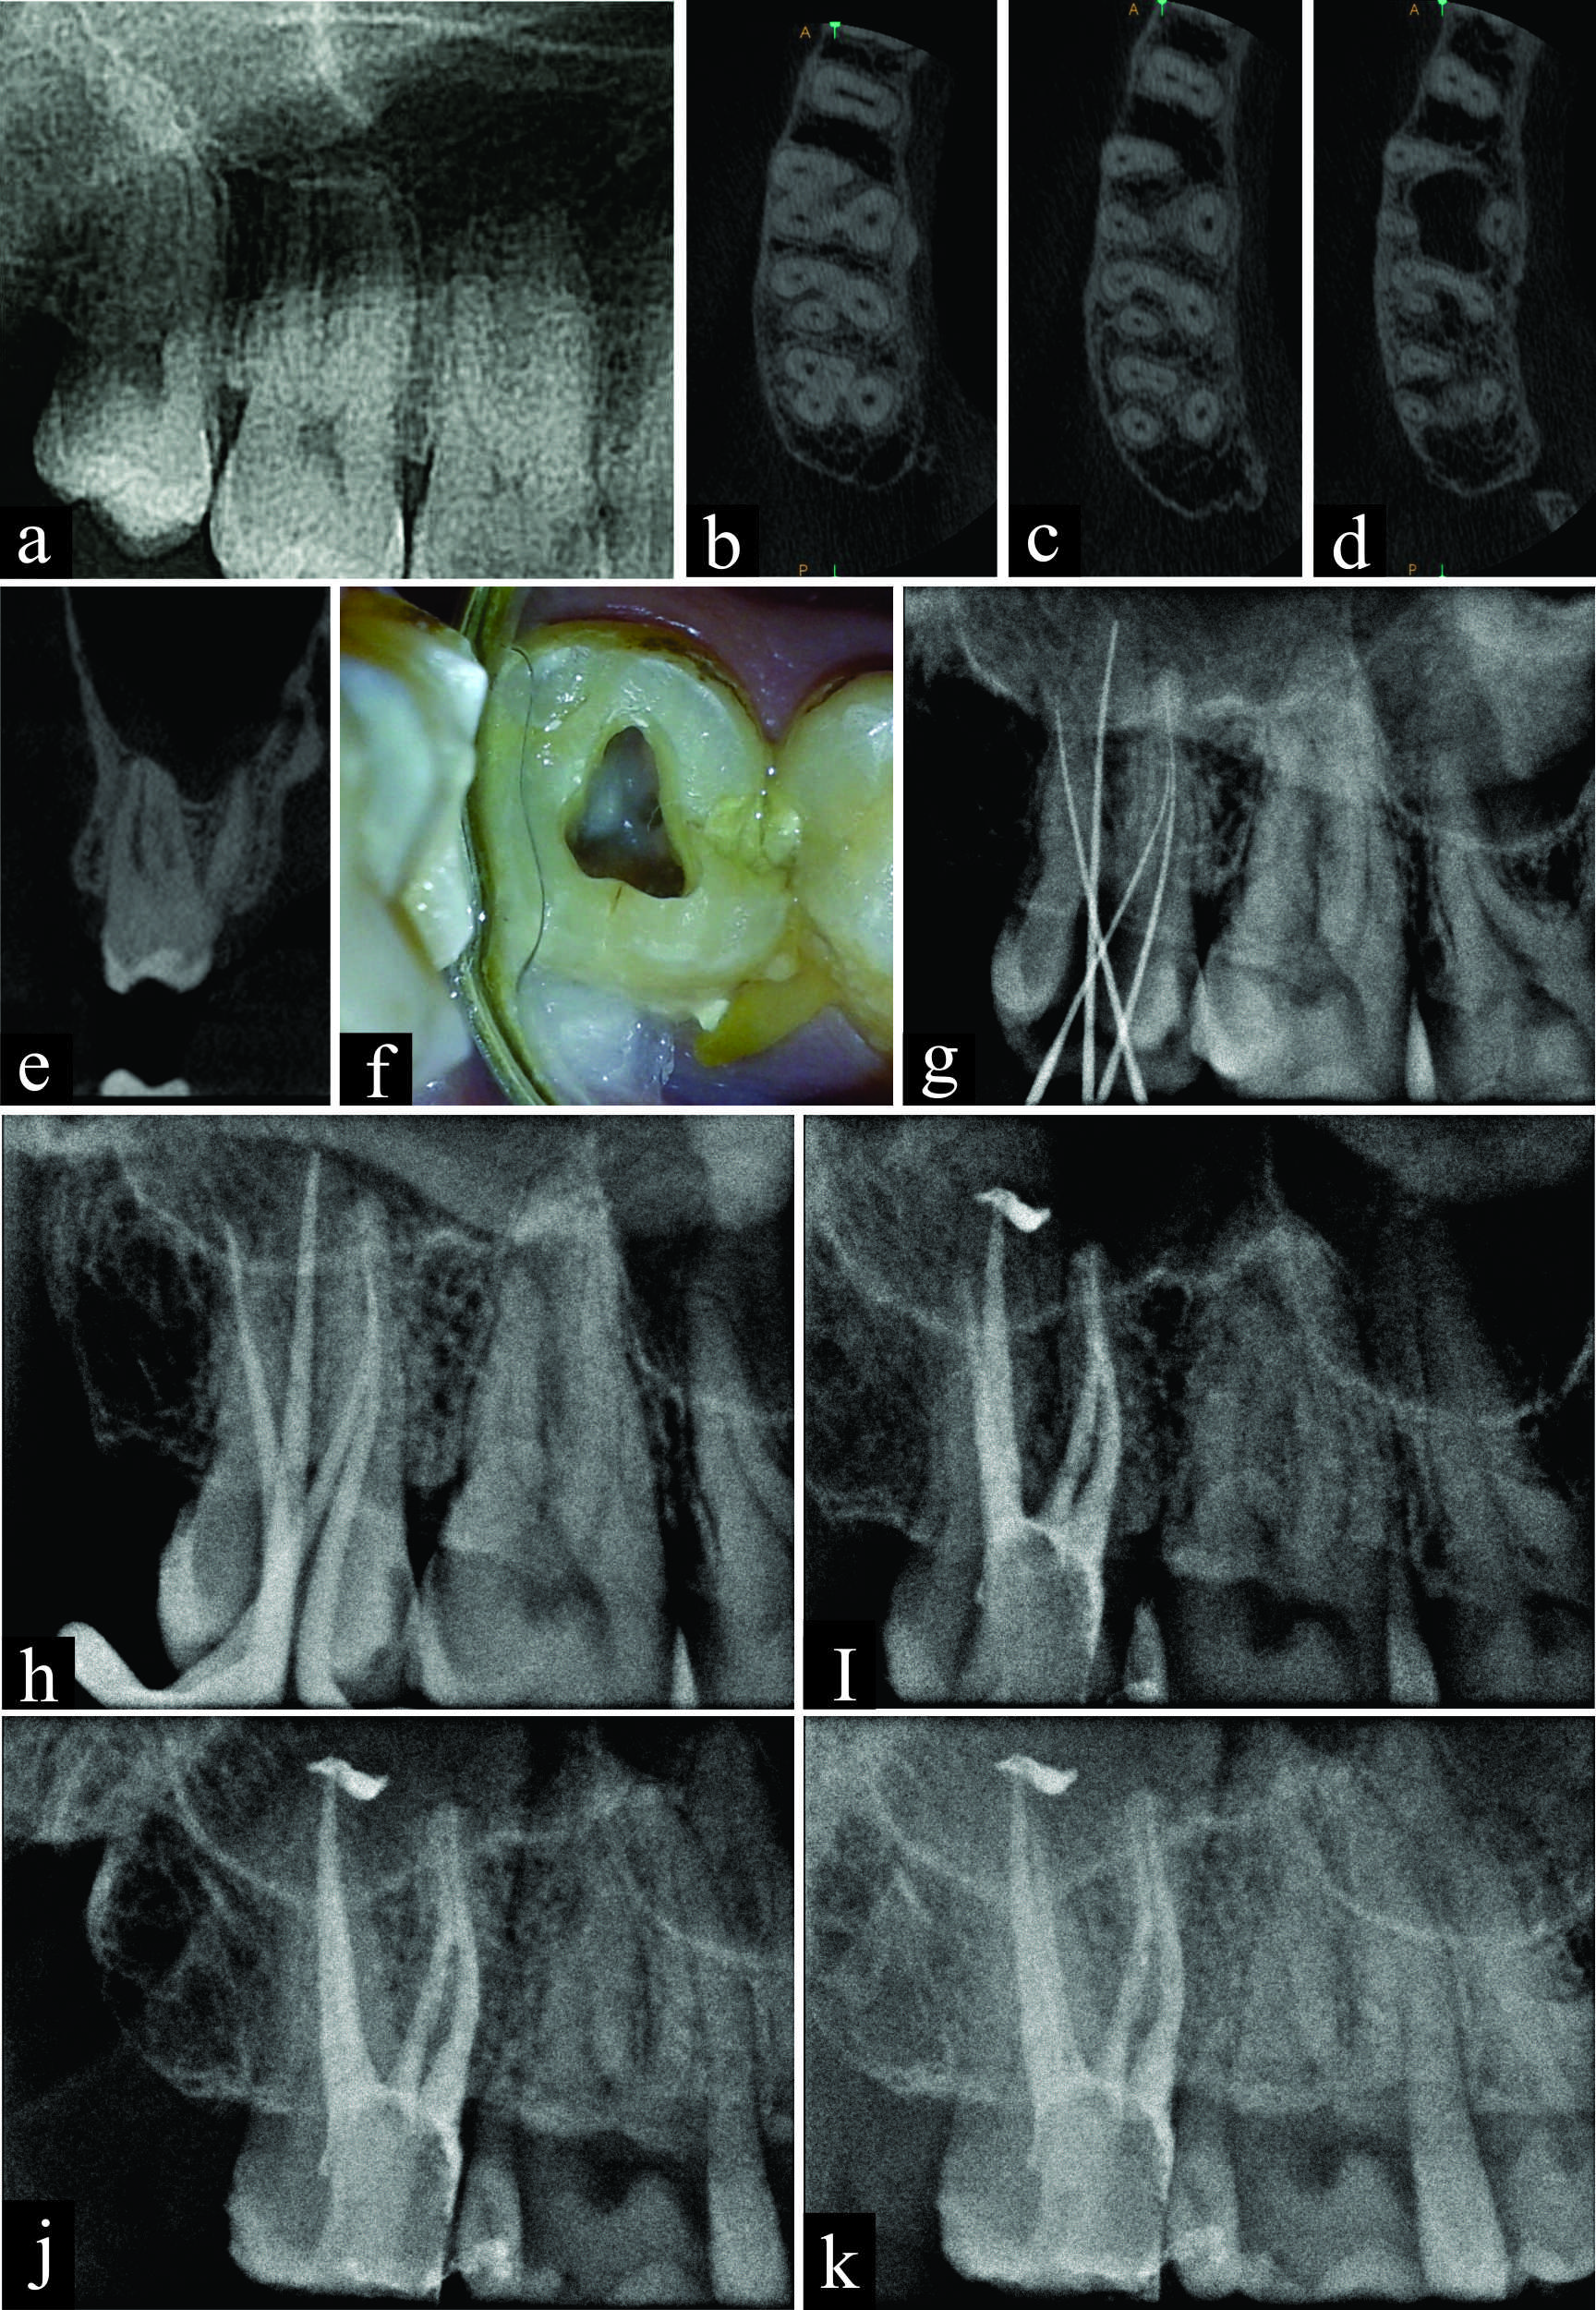

Endodontic management of maxillary third molar with MB2 (Vertucci type IV) canal configuration diagnosed with Cone Beam Computed Tomography – a case report

The endodontic treatment of maxillary third molar often poses a challenge even to an experienced endodontist because of their most posterior location in the dental arch, aberrant occlusal anatomy, abnormal root canal configuration and eruption patterns. Owing to these anatomical limitations, their extraction remains the treatment of choice for many clinicians. As we know, retaining every functional component of the dental arch is of prime importance in contemporary dental practice. This clinical case report aims to discuss the endodontic treatment of maxillary third molar with MB2 root canal separated throughout the length and exit at two separate apical foramina (Vertucci type IV) diagnosed with Cone Beam Computed Tomography (CBCT).